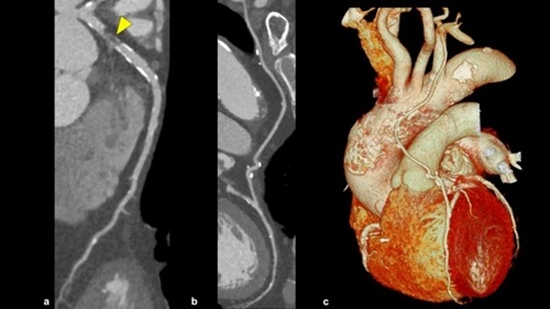

Investigation of the frequency of stent strictures in coronary arteries after stenting by CT

In our study, the relationship between the gender of the patients and the frequency of stents and stenosis in them was investigated, and the results showed that, in general, the frequency of stent restenosis is the same in men and women (p=95%). The analysis showed that in the RCA vein, the percentage of complete obstruction in the stent in women is significantly higher than that of men (29.8% vs. 5%), while in the LAD vein, there is a significant difference in terms of the percentage of restenosis. Stent was not observed in women and men, but in LM and lcx veins The possibility of repeated stenosis is more in men than in women. The results showed that in all three vessels, the 256 device is able to detect restenosis with greater ability than the 64 device, and the difference is statistically significant (p<0.0001). The Slic MDCT256 device not only shows the stenosis of coronary arteries and CABG vessels well, but also has high sensitivity and specificity in detecting restenosis of stents. Due to the fact that the LM vein is the main trunk of the coronary arteries and the narrowness in it is less likely to be stented, and re-stenosis in its stents is less in both men and women. The highest percentage of stenting is in the LAD vein, and the probability of restenosis in the stents of this vein is also higher than in other coronary arteries.